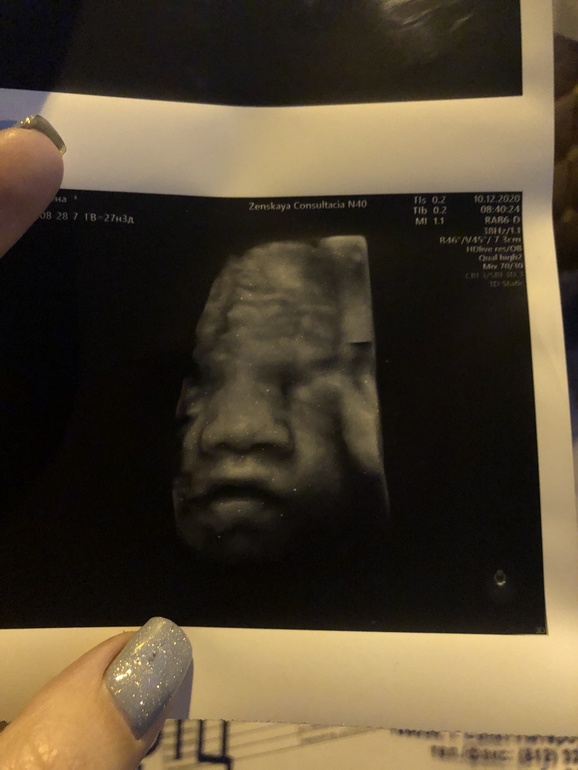

3Д узи в 27нед и 4дн

УЗИ, КТГ, доплерНашла я все таки где его сделать, в своей ЖК))))

Малышка осталась малышкой, ничего не выросло

Лежит уже в головном

соответствует сроку 26/27 нед, окружность головы и животика как поняла чуть ниже среднего, но в пределах , и как итог- соответствие своему сроку, т.е. там прям посредине почти кружок) врач это все показала

Вес -1010гр

ЧСС-140

Шейка-38мм

Амниотический индекс-125мм

Плацента по задней на 4см выше зева

Толщина плаценты-26мм 0 ст.зр

Кровотоки в норме

Ноги руки нормальный длины

Окружность живота 21,82

Окр головы-25,38

БПР-6,98

Сказали небольшая малышка будет

Малышка закрывала личико руками, сфоткали сбоку только)

Говорит губехи хорошие

и нос тоже не кнопочка🤣🤣🤣 есть в кого так скзаать, у меня длинный, у мужа еще больше))))